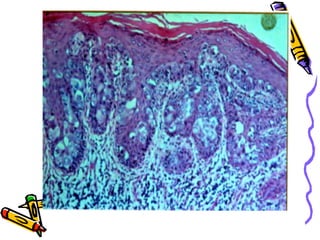

This document discusses benign and malignant diseases of the vulva. It begins by outlining common symptoms of vulvar diseases such as itching, burning, and bleeding. It then provides an overview of the general pathology and terminology used to describe vulvar diseases. The document categorizes vulvar lesions as white, red, or brown/bluish and discusses specific conditions that present with each color, including vitiligo, lichen sclerosis, squamous cell hyperplasia, infections, dermatitis, and various precancers and cancers. Treatment options are provided for some conditions like HPV. Throughout, it emphasizes the importance of inspection, palpation, biopsy prior to treatment, and using medical therapy for benign lesions.